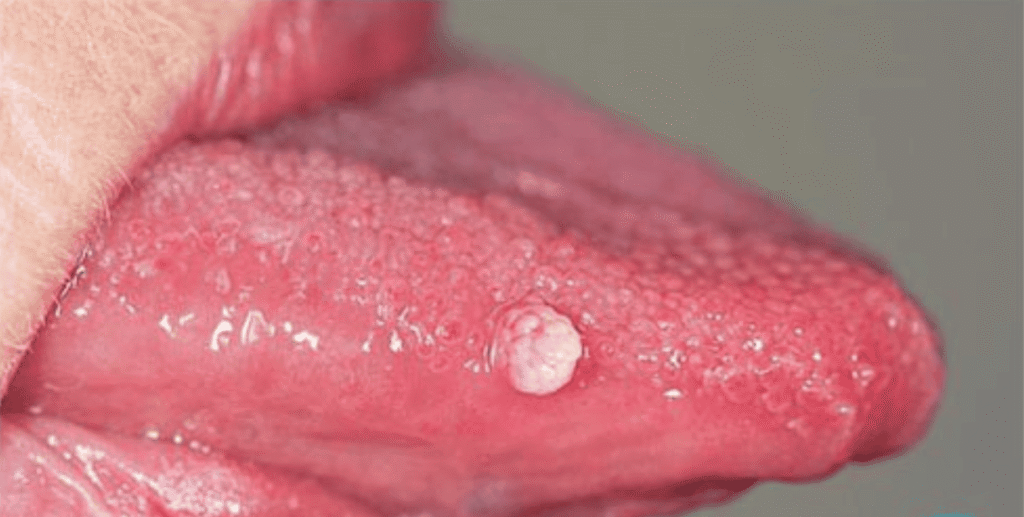

علائم زگیل دهانی

Symptoms of oral warts

برخی اوقات نماهای نرمال دهان مثل جوانه های چشایی زبان با ضایعات اچ پی وی دهانی اشتباه گرفته میشوند. برای تشخیص و اطمینان از ابتلا به اچ پی وی دهانی بهترین گزینه مراجعه به متخصص بیماری های دهان است.

این ویروس از طریق تماس مستقیم پوست یا مخاط، مانند بوسیدن، رابطه جنسی دهانی یا تماس نزدیک منتقل میشود. اکثر افراد مبتلا به HPV دهانی هیچ علامتی ندارند و خودشان هم نمیدانند که ویروس را دارند و میتوانند موجب سرایت ویروس به شریک جنسی خود بشوند . این ویروس بیش از 200 نوع مختلف دارد که میتوانند باعث ایجاد ضایعات گلکلمیشکل کوچک روی پوست، ناحیۀ تناسلی و دهان بشوند. ابتلا به این ویروس در بسیاری از مواقع هیچ علامتی ندارد و در افراد با سلامت جسمی خوب، بدون درمان، طی ۱-۲ سال از بدن پاک میشود؛ اما برخی اوقات سیستم ایمنی بدن قادر به حذف ویروس نبوده و برای سالها میتواند در بدن به شکل نهفته باقی بماند. دقیقا مشخص نیست که چرا این ویروس در برخی افراد به راحتی از بدن حذف شده و در برخی دیگر شکل مزمن پیدا میکند اما احتمالا این امر مرتبط با کارآمدی سیستم ایمنی فرد و یا نوع ویروس HPV است. در صورت وجود ضایعات پوستی مخاطی، این ضایعات خود به خود برطرف نمیشوند و حذف آنها نیاز به مداخلات درمانی دارد. این ضایعات منبع انتقال عفونتاند و تماس با آنها میتواند منجر به سرایت ویروس به افراد دیگر شود. برخی سویههای این ویروس، بهویژه انواع 16، 18، 31 و 33 با افزایش ریسک ابتلا به سرطانهای گردن رحم و ناحیۀ حلق و خلف دهان مرتبطاند؛ به عبارت دیگر، در افراد مبتلا به این سویههای ویروس پاپیلومای انسانی احتمال ابتلا به سرطانهای دهان و رحم بیشتر از افرادی است که به این ویروس مبتلا نیستند.

معاینۀ کامل دهان توسط متخصص بیماریهای دهان انجام میشود. درصورت مشاهدۀ ضایعه، برداشت ضایعه توسط لیزر و در برخی مواقع، توسط برش با تیغ و بخیه انجام میشود. ضایعه برای تعیین سروتایپ (نوع ویروس) و همچنین، تشخیص قطعی به پاتولوژی فرستاده میشود. درصورتیکه ضایعه مرتبط با سویههایی با ریسک بالا برای ایجاد سرطانهای دهان (انواع 16 و 18) باشد، بررسی دورهای منظم به بیماران توصیه میشود.